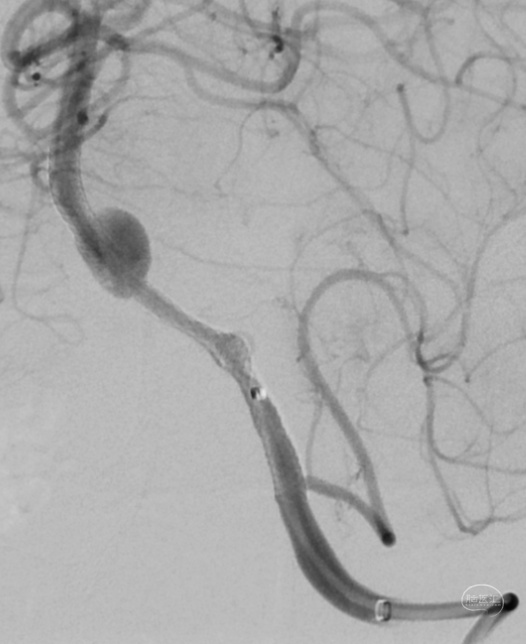

DSA:

3D重建显示基底动脉下部、双椎结合部、左椎多发夹层动脉瘤: